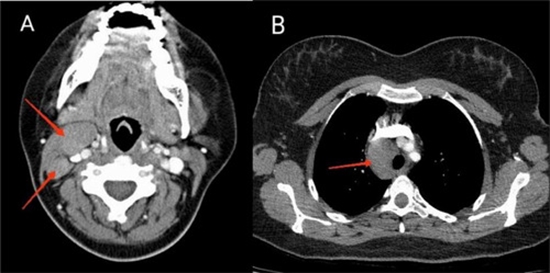

Vanishing bile duct syndrome related jaundice as the first presentation of Hodgkin lymphoma

Vanishing bile duct syndrome is a rare, acquired disease that has been described in different pathologic conditions' including adverse drug reactions, autoimmune diseases, graft vs host disease, and neoplasms. It is a condition characterized by progressive loss of intrahepatic bile ducts leading to ductopenia and cholestasis. Here we report a 27-year-old female who presented with jaundice and cholestatic hepatitis and was finally diagnosed with vanishing Bile duct syndrome secondary to Hodgkin lymphoma. Physicians need to consider a range of differential diagnoses, especially malignancies, in suspected cases of vanishing bile duct syndrome.